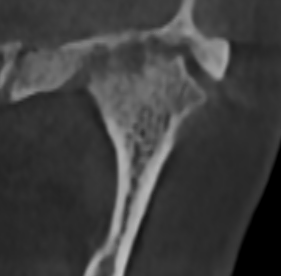

Перед началом лечения я провожу часовую первичную консультацию. Для этой встречи вам необходимо сделать «МРТ ВНЧС» и «КЛКТ двух челюстей с захватом ВНЧС в привычном прикусе».

Во время консультации мы смотрим и анализируем ваши исследования. Я подробно объясняю строение ВНЧС, показываю все причинные факторы вашей проблемы, отвечаю на все вопросы «Почему?»